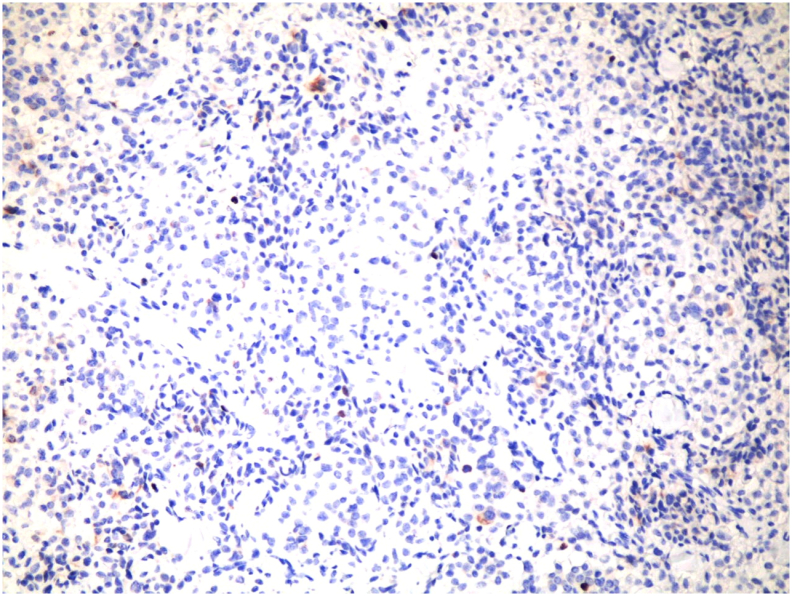

The pathology [Fig. 4, Fig. 5] showed a proliferation of pleomorphic round to oval cells with a moderate amount of finely granular cytoplasm. The nuclei show a salt and pepper appearance. The mitotic index is less than 1mitosis/10HPF. The tumor cells are invading the mucosa of the common bile duct and the surrounding fat. Perineural invasion and lymphovascular invasion are seen. Chromogranin and Synaptophysin immunohistochemical stains were done, and they were positive in the appearing neuroendocrine cells and the signet appearing cells. Ki67 immunohistochemical stain was positive in less than 2% of the tumor suggestive of well-differentiated neuroendocrine carcinoma, grade 1.